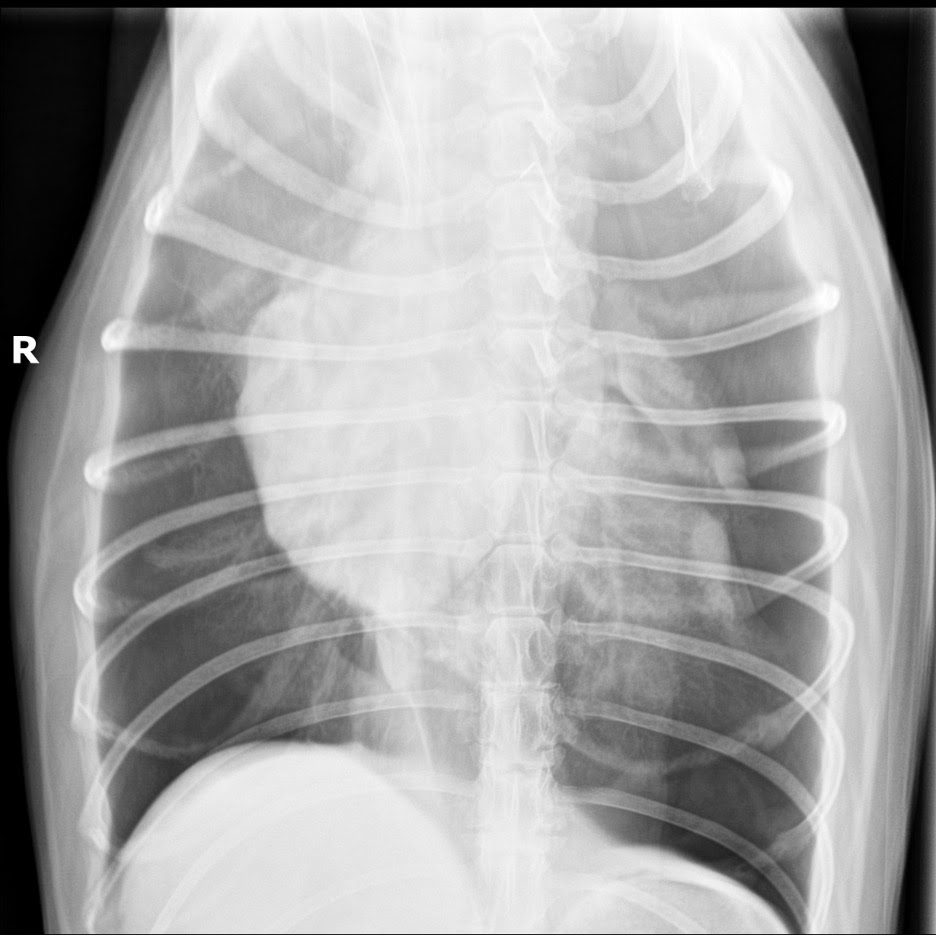

Approximately 1600 mL of air was aspirated by thoracocentesis. Serial radiographs confirmed significant improvement in free air volume, and the patient’s condition stabilized.

- Large-volume, bilateral pneumothorax

- Pulmonary alveolar pattern secondary to atelectasis

- No obvious lymphadenopathy

Radiographs have high sensitivity for diagnosing pneumothorax; however, they are significantly less sensitive and specific than CT in detecting underlying cause and/or extent of disease. Primary spontaneous pneumothorax is generally caused by one or multiple pulmonary blebs or bullae. CT has been shown to identify bullae up to 2.5 times more often than radiographs, which provides useful information regarding prognosis and surgical planning. CT can still miss 40–50% of bullae, however, and maintaining negative thoracic pressure with indwelling thoracostomy tubes can improve lesion identification.